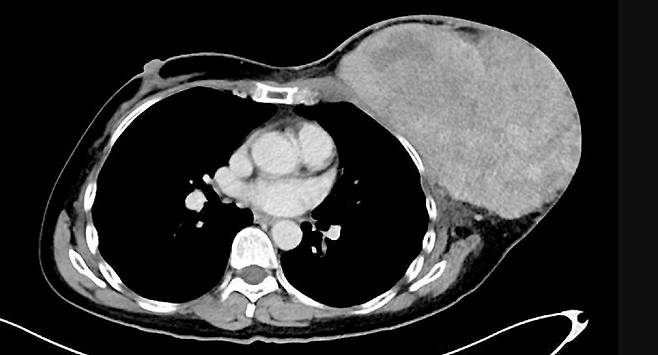

싱가포르 KK 여성·어린이 병원 의료진은 54세 여성 A씨가 6개월 사이에 왼쪽 가슴 안쪽 덩어리가 커지고, 가슴이 불편해지는 증상으로 병원을 찾았다고 밝혔다. 검사 결과, 유방암일 때 나타나는 젖꼭지 분비물이나 피부가 함몰되는 등의 변화는 없었다. 과거 암 병력도 없었으며 평생 술이나 담배도 하지 않았다. CT 촬영을 했더니 왼쪽 가슴에서 약 17cm 크기의 덩어리가 보였다. 암일 가능성이 있어 덩어리를 완전히 몸에서 절제해내는 수술을 해야 했다. 덩어리 크기가 너무 커서 제거 이후 왼쪽 허벅지 등의 피부를 일부 이식해야 했다. 다만, 다행히도 최종 조직학적 검사에서 덩어리가 암이 아닌 '양성 엽상종'으로 드러났다. 정확한 부피는 18cm x 19cm x 8cm나 되는 것으로 확인됐다. 종양 제거 수술 후 A씨는 다행히 잘 회복됐고, 수술 후 5일째에 집으로 돌아갔다.